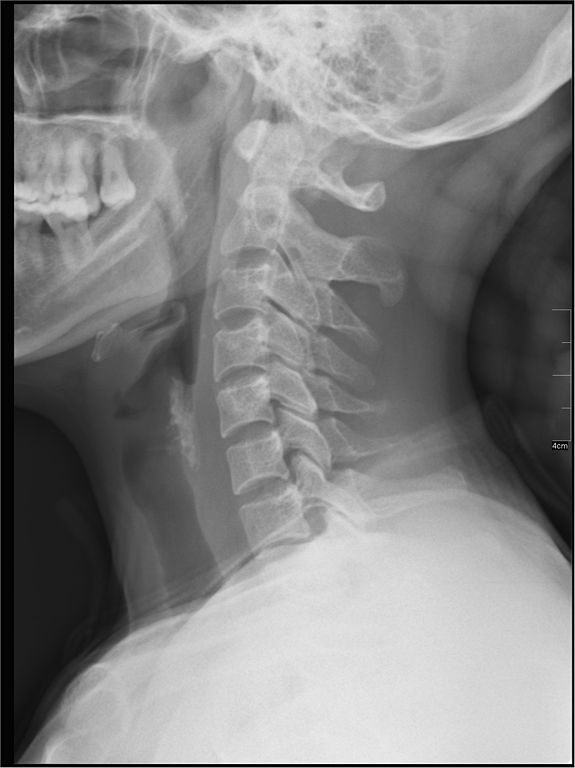

Headaches can come from many causes, and one common problem is our posture. We do so many things in front of us and down – using the computer, phones, driving, etc. The normal C-shaped curve in the neck (called cervical lordosis) slowly decreases and can even start to curve in the opposite direction!